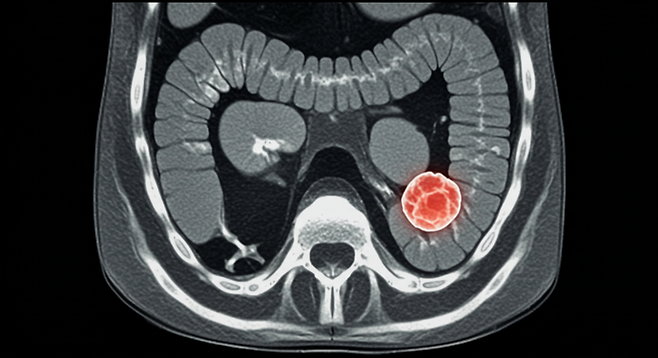

용종과 대장암의 연관성

대장 용종은 대장의 점막에서 자라는 작은 혹으로, 대부분은 무해하지만 일부는 시간이 지나면서 암으로 발전할 가능성이 있습니다. 연구에 따르면, 특정 음식과 식습관이 용종 발생 위험을 증가시킬 수 있으며, 특히 가공육과 정제 탄수화물이 주요 원인으로 꼽힙니다.